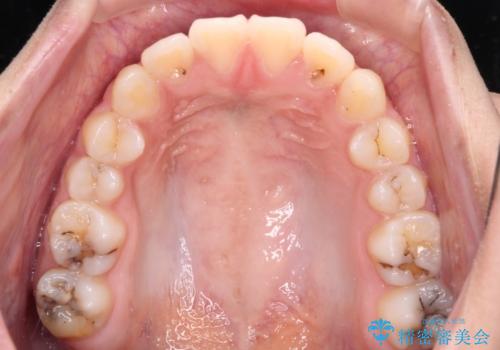

- 下顎の前突感と前歯の叢生を気にして来院された患者様です。

下顎前方位の骨格のため、下顎歯列に対して上顎歯列の幅が狭くなっていました。

急速拡大装置を用いて上顎骨を側方に拡大し、上顎の叢生を解消するとともに下顎歯列拡大により下顎の叢生も解消することとしました。